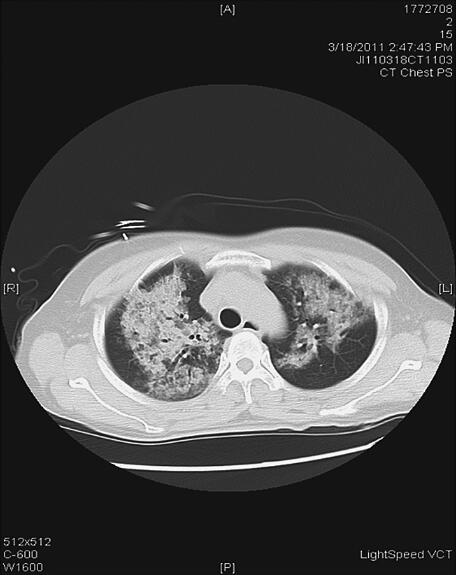

辅助检查:2011年3月18日血常规:WBC 15.97×109/L,N 89.5%,Hb 179g/L,PLT 142×109/L,肝肾功能、心肌酶正常,血糖19.8mmol/L,TNT(−),D-二聚体0.65ng/ml,BNP>5000pg/ml;尿常规:比重1.025,尿糖(++++),尿酮体(+++),尿蛋白微量;血气分析示:pH 7.17,PO2 68mmHg,PCO2 16mmHg,5.8mmol/L,SaO2 87%;胸片(1)示双肺纹理增多、模糊,可见多发片状模糊影,以右上肺为著,双肺门模糊,心影大小及形态未见异常,两膈面光滑,肋膈角锐利;胸部CT(图2)示双肺广泛分布斑片、团片状磨玻璃影,边界模糊,纵隔未见明显肿大淋巴结,心影无明显增大。诊断双肺多发病变——感染?肺水肿?ECG示窦性心动过速,非特异性T波改变。超声心动图示左心室壁运动弥漫减低,主动脉瓣反流(轻度),三尖瓣反流(轻度),LVEF 25%。

图2 入院时CT示双肺广泛分布斑片、团片状磨玻璃影,边界模糊,纵隔未见明显肿大淋巴结,心影无明显增大